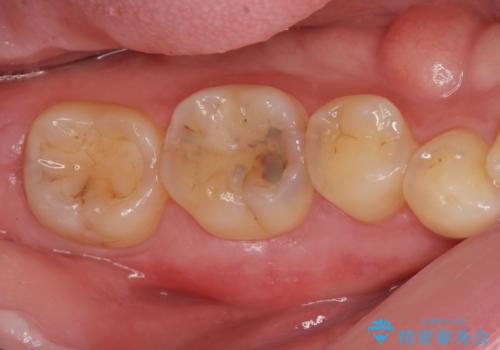

セラミックインレー。

- セラミック治療希望の患者様です。

古い樹脂の材料をとりe-maxの詰め物で治療を行いました。

適合の良い詰め物が入りました。